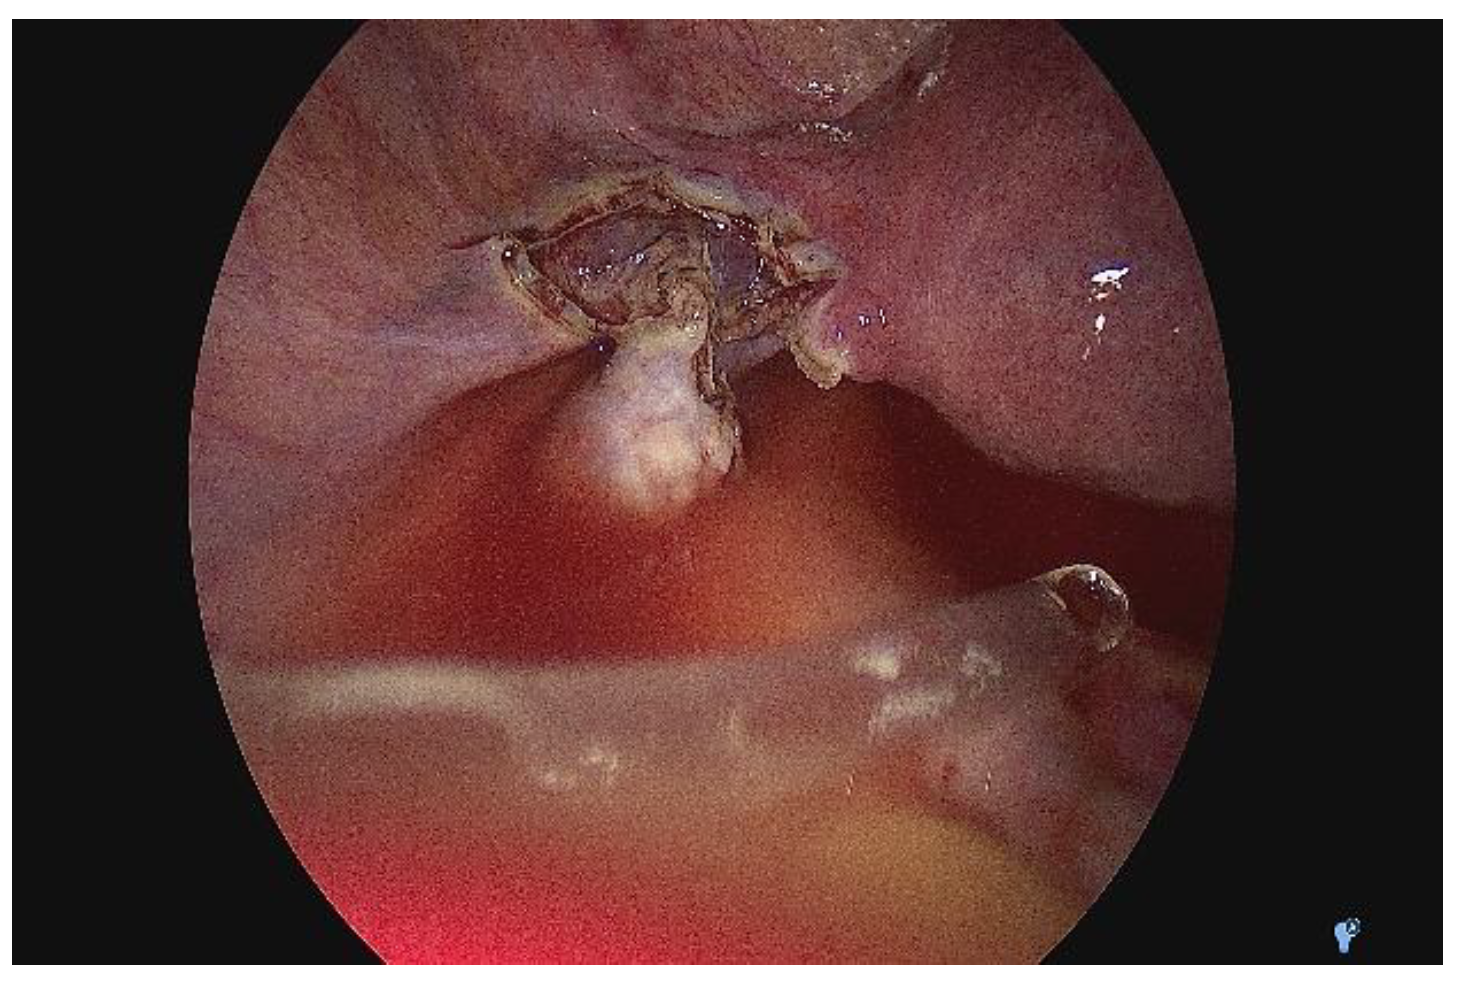

2. Case Presentation

2.2. Clinical History

2.3. Diagnostic Assessment and Investigations